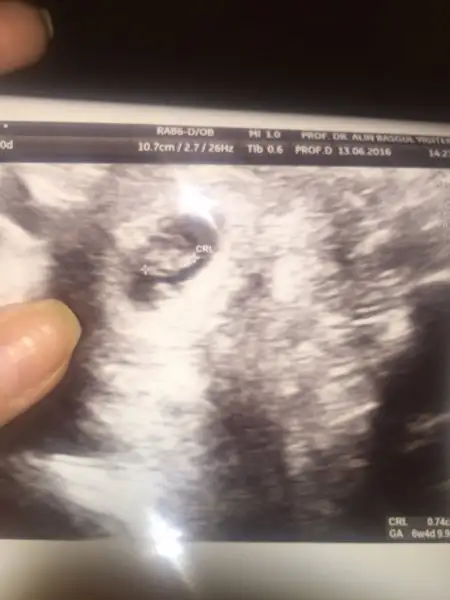

Havalianne__ merhaba canim bugun kontrole gittik 7+5 ama usg ye gore 8 haftalik cikti karindan bakildi burda saga yakin sanki

Bir onceki sayfada attigim usg de 6+3 tu ordada 6+2 cikmisti ama sola yakindi yine karindan bakilmisti erkek gibi dedin ama bugun ki usg kafami karistirdi yine yorumlarsan sevinirim sence nedir bebegimin cinsiyeti

Anladim canim eger oyleyse ikinci oglum geliyor saglikla gelsin kesinlesince yazarim sana tesekkur ederimEvt cnm plasenta ve bebekte sağda ama ilk usg daha onemli